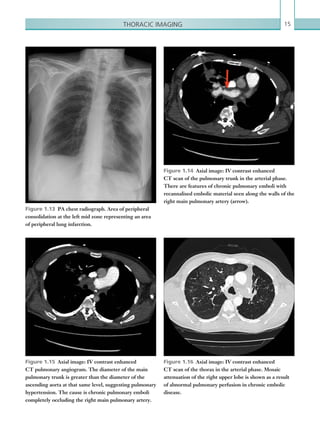

Figure 1.13  PA chest radiograph. Area of peripheral

consolidation at the left mid zone representing an area

of peripheral lung infarction.

Figure 1.14  Axial image: IV contrast enhanced

CT scan of the pulmonary trunk in the arterial phase.

There are features of chronic pulmonary emboli with

recannalised embolic material seen along the walls of the

right main pulmonary artery (arrow).

Figure 1.15  Axial image: IV contrast enhanced

CT pulmonary angiogram. The diameter of the main

pulmonary trunk is greater than the diameter of the

ascending aorta at that same level, suggesting pulmonary

hypertension. The cause is chronic pulmonary emboli

completely occluding the right main pulmonary artery.

Figure 1.16  Axial image: IV contrast enhanced

CT scan of the thorax in the arterial phase. Mosaic

attenuation of the right upper lobe is shown as a result

of abnormal pulmonary perfusion in chronic embolic

disease.